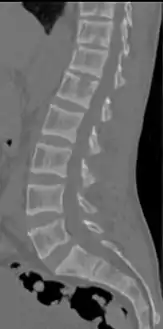

Renal osteodystrophy is usually diagnosed after treatment for end-stage kidney disease begins; however the CKD-MBD starts early in the course of CKD.[1][6] In advanced stages, blood tests will indicate decreased calcium and calcitriol (vitamin D) and increased phosphate, and parathyroid hormone levels. In earlier stages, serum calcium, phosphate levels are normal at the expense of high parathyroid hormone and fibroblast growth factor-23 levels. X-rays will also show bone features of renal osteodystrophy (subperiostic bone resorption, chondrocalcinosis at the knees and pubic symphysis, osteopenia and bone fractures) but may be difficult to differentiate from other conditions. Since the diagnosis of these bone abnormalities cannot be obtained correctly by current clinical, biochemical, and imaging methods (including measurement of bone-mineral density), bone biopsy has been, and still remains, the gold standard analysis for assessing the exact type of renal osteodystrophy.[6][15]